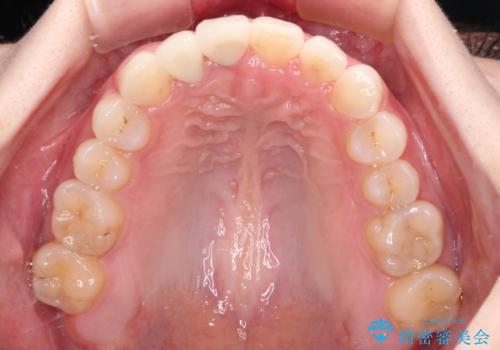

- 一度矯正治療を希望して始めたものの断念し、前歯をセラミッククラウンで治療した後に、やはり矯正でしっかり治したいとのことで来院された患者様です。

当初、前歯の歯列矯正を希望して銀座院に来院され、補助装置を装着するところまで進んだのですが断念してしまいました。

その後、他院で気になる前歯をセラミッククラウンで補綴治療をしたそうですが、やはり歯列を整えたいとのことで再度来院されました。

クラウンの状態は、根管治療の状態も含めて決して良い状態とは言えず、矯正治療後の根管治療と補綴治療の再治療を前提として、インビザラインによる矯正治療を行うこととしました。

治療前、下顎前歯はほとんど見えない咬み合わせでしたが、矯正治療によりディープバイトが改善されました。

矯正治療中に前歯2本のクラウンは外れてしまい、途中仮歯に替える必要があったので期間は掛かりましたが、歯列も整い、負担のかからない咬み合わせを達成することができました。